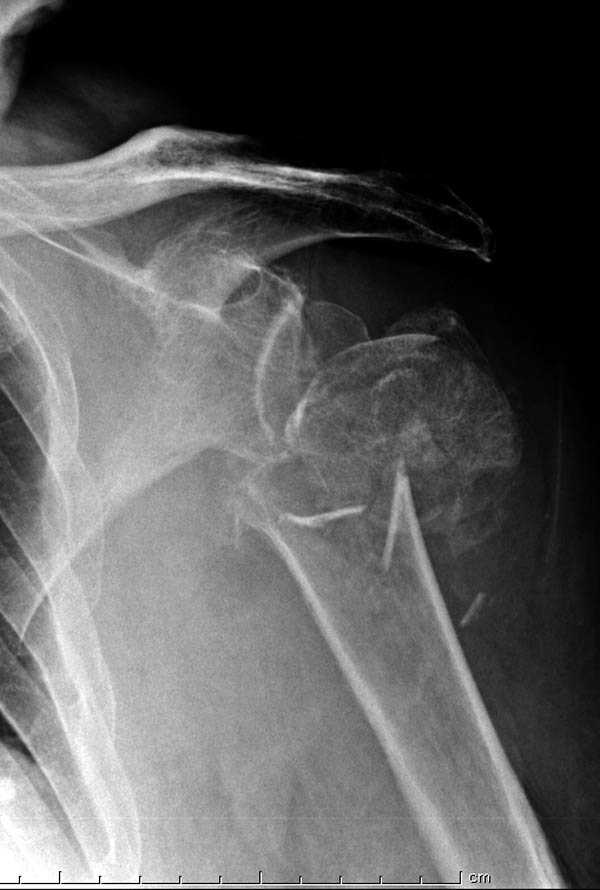

дополнительные снимки по протезированию